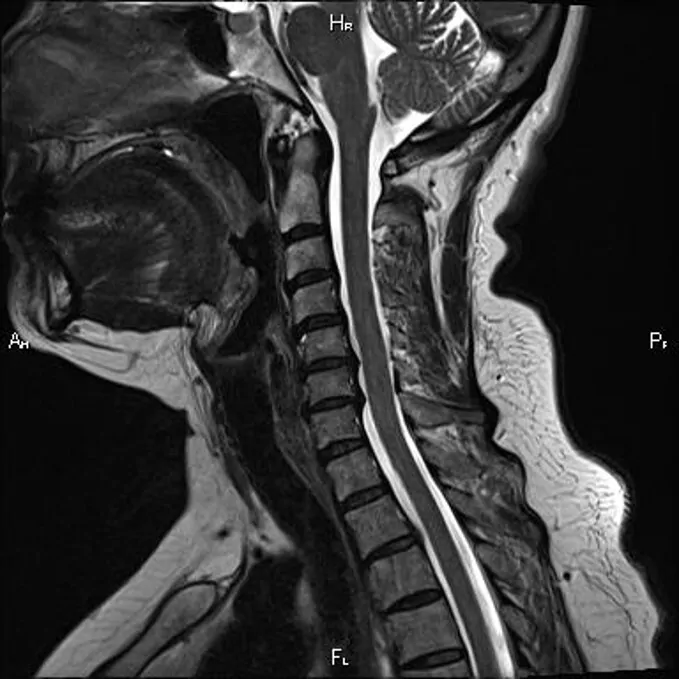

МРТ шейного отдела. https://mrtpetrograd.ru/webp/original/assets/img/gallery/license/2730935e82a33cb6d17aeafd1ca5ed47.jpg.webp